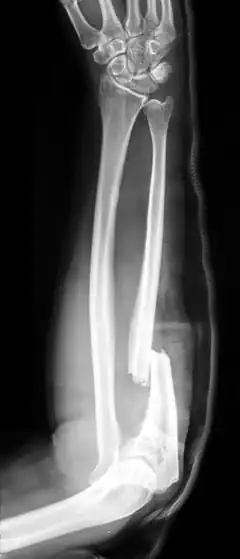

- Monteggia fracture - a fracture of the near to elbow end of the ulna with the dislocation of the head of the radius at the elbow joint.[3]

Monteggia fracture (type of ulna fracture) -

Monteggia fracture (fracture of proximal ulna) -